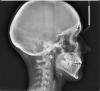

Один из ортодонтов поставил открытый прикус, а другой - прямой с тенденцией к мезиональному. + тесное положение зубов на верхней и нижней челюсти, 1 кл по Энглю.

Сказали удалять восьмерки.

И возможно 5ки на нижней челюсти.

Что же делать с таким прикусом, большая вероятность рецидива после ношения брекетов?)